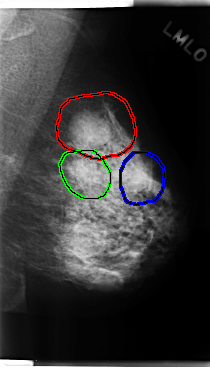

C_0223_1.LEFT_MLO

FILE: C_0223_1.LEFT_MLO.OVERLAY

TOTAL_ABNORMALITIES 3

ABNORMALITY 1

LESION_TYPE MASS SHAPE OVAL MARGINS CIRCUMSCRIBED

ASSESSMENT 3

SUBTLETY 5

PATHOLOGY BENIGN

TOTAL_OUTLINES 1

BOUNDARY

ABNORMALITY 2

LESION_TYPE MASS SHAPE OVAL MARGINS OBSCURED

SUBTLETY 3

ABNORMALITY 3

SUBTLETY 4